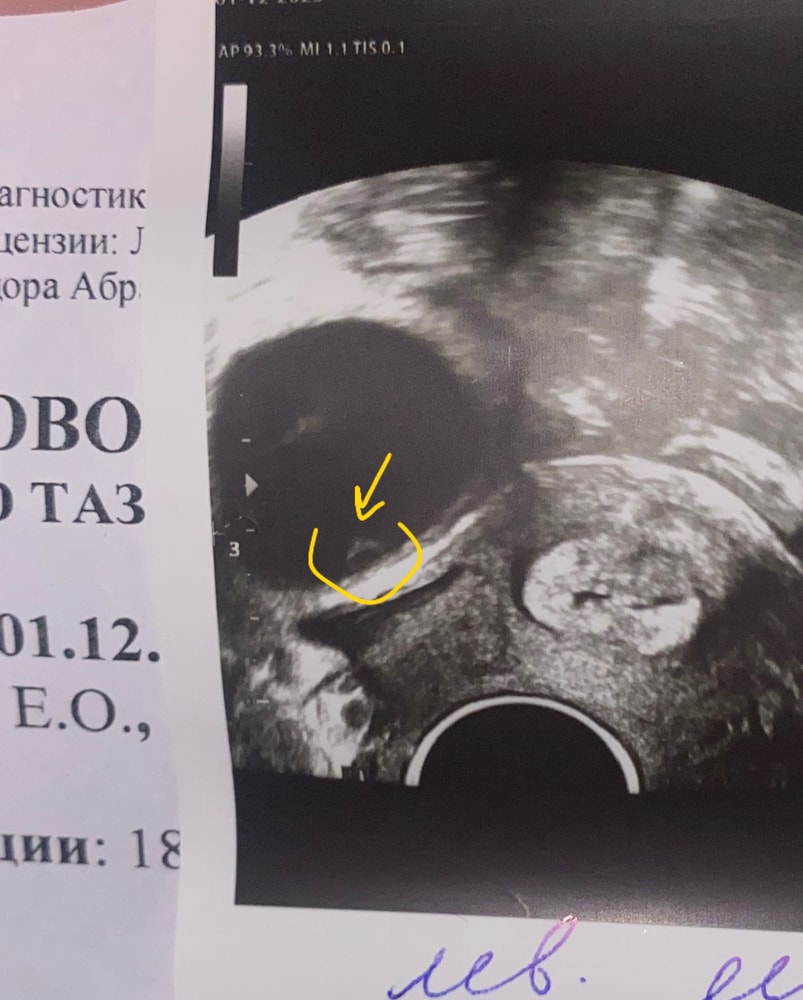

а интересно , вот на фото где ДФ обвела желтым это яйценостный бугорок или у меня разыгралось воображение ?

Фолликул опять 30 мм!

———-Даже не знаю уже, какие то проблемы у меня или тенденция и это норма для моего организма. Эндометрий в этот раз еще толще аж 14,5 мм